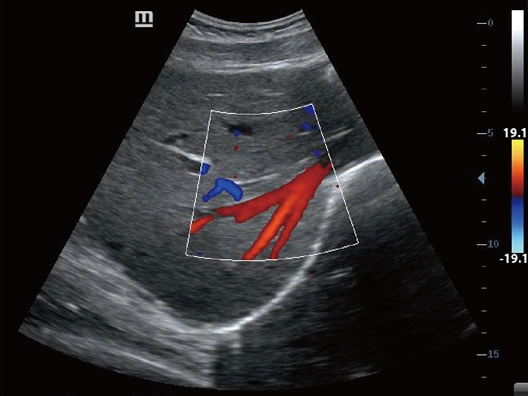

Клинические изображения

- Режимы сканирования: B/M/Color Dopler/Color M/Power/Directional Power Doppler Flow Imaging

- NTE (компрессионная эластография), поддержка исследований с контрастом и широкий выбор опций для акушерства/гинекологии, в том числе в режиме 3D/4D.